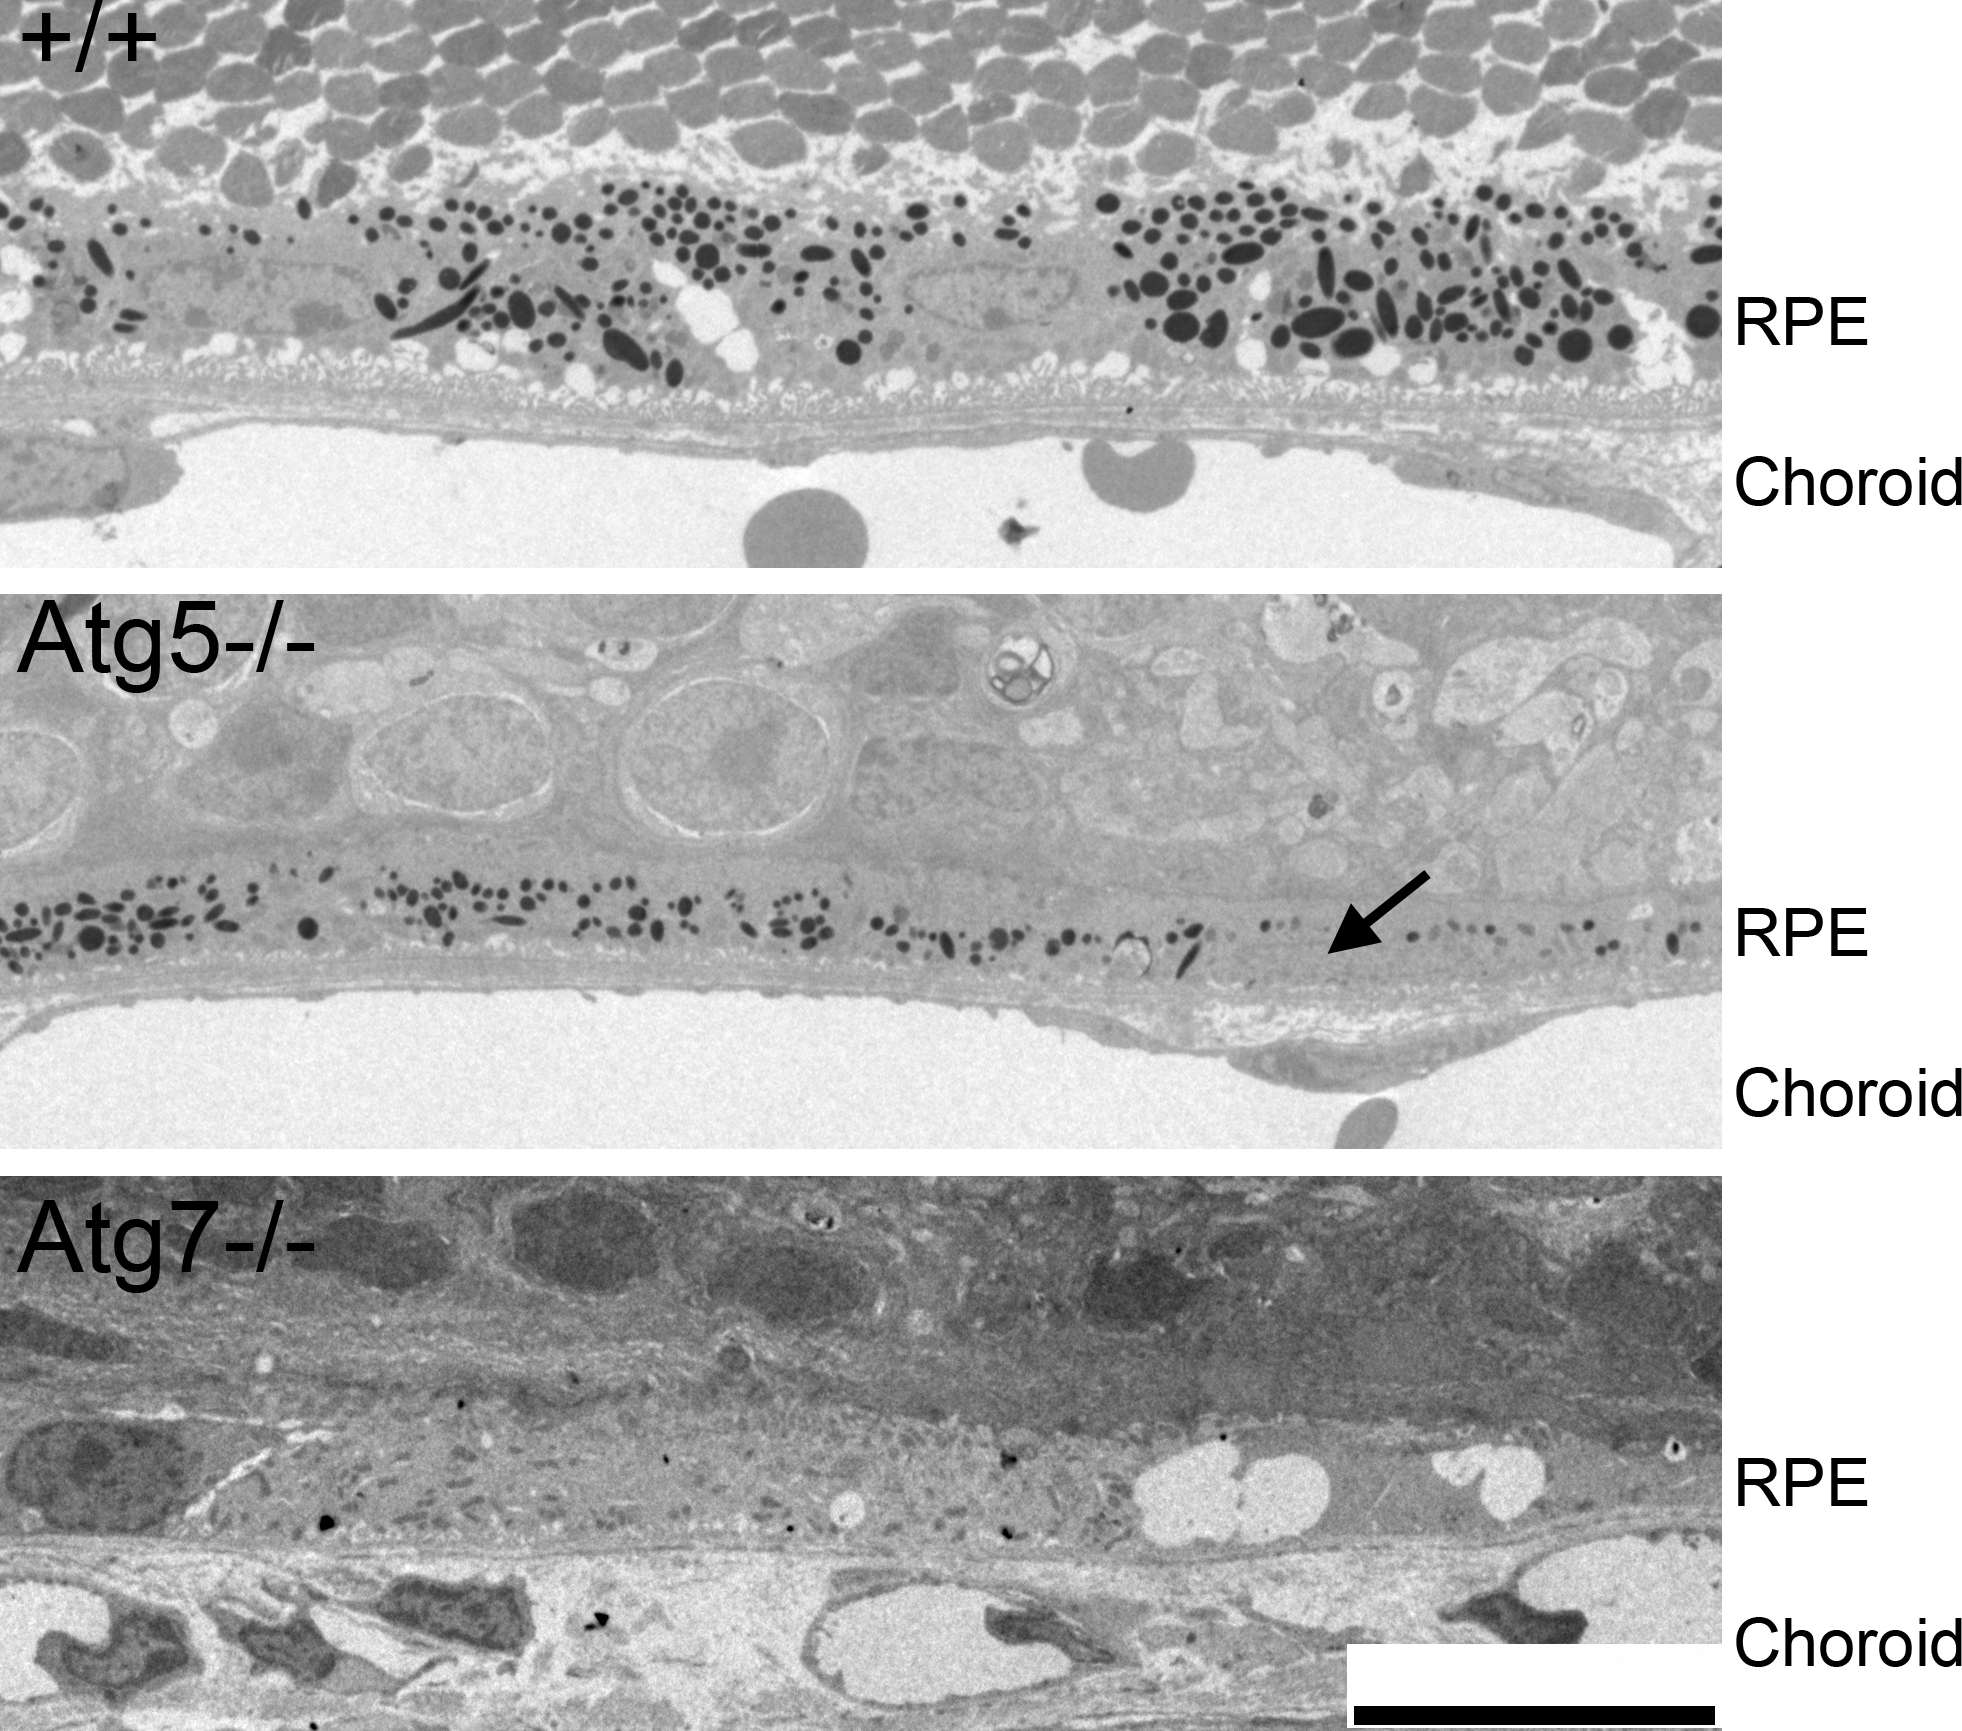

Figure 7. Thinned RPE in aged Atg5ΔRPE and Atg7ΔRPE mice. Representative electronic micrographs showing the RPE region of the 17-month-old wild-type (+/+), Atg5ΔRPE (Atg5−/−), and Atg7ΔRPE (Atg7−/−) mice. Note that the RPE thicknesses of the Atg5ΔRPE and Atg7ΔRPE mice are approximately one third to one half that of the wild-type mice. The wild-type and Atg5ΔRPE mice shown were pigmented, and the Atg7ΔRPE mouse was albino. Arrow indicates a hypotrophic RPE cell. Scale bar = 10 µm.